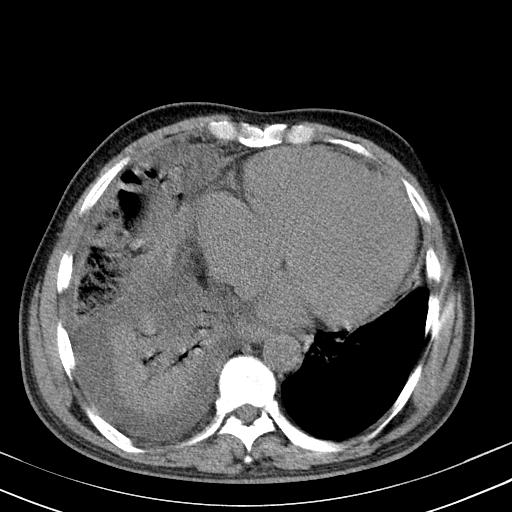

以下是引用zxl51642在2010-3-21 17:06:00的发言:[br]右下中心型肺癌并阻塞性肺炎/不张,纵膈淋巴结肿大,右侧大量胸腔积液,左侧少量胸腔积液,少量腹水。建议纤维支气管镜进一步检查。